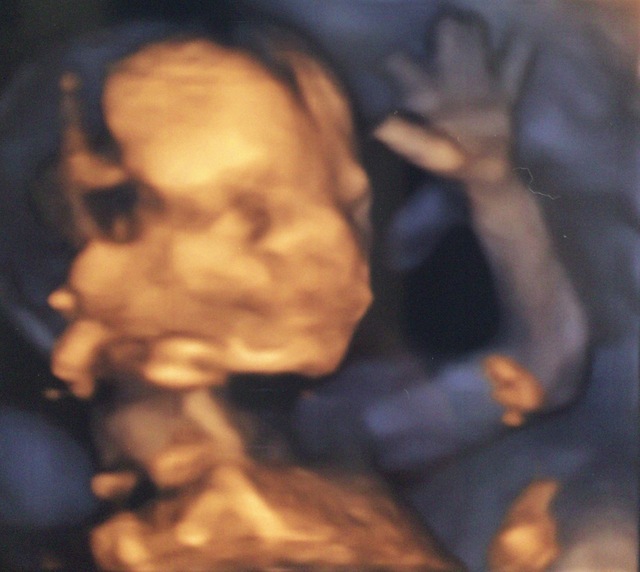

16週0日(16w0d・女の子)|aiscream さん(27歳)

エコー写真撮影時のエピソード:

初めての妊娠。 どんどん大きくなる赤ちゃんの姿を楽しみに 待ちに待った健診 (o^^o)

元気な心臓の音を聞かせてくれて、 エコーも終盤になった頃 やっほー♪またねー♪ と言わんばかりに赤ちゃんが右手を上げて手を振ってくれたときの1枚です♡♡

※こちらのエコー写真は第1回「コズレエコー(超音波)写真コンテスト」の受賞作です!